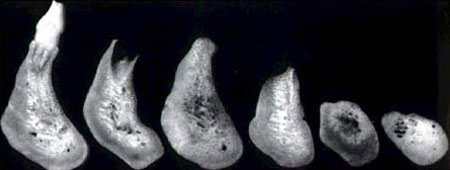

Die Folgen eines Zahnverlusts führen neben der reduzierten Kaufunktion und Ästhetik vor allem zu einem Knochenverlust. Die Ursachen sind in der fehlenden bzw. unphysiologischen Kaukrafteinwirkung. In extremen Fällen kann der Kiefer so weit schrumpfen, dass ein Prothesenhalt nicht mehr möglich ist, und sogar der Kiefer bei extremen Fällen brechen kann.

Mit Hilfe von Knochenersatzmaterialien ist es möglich, den Kieferaufbau nach Zahnentfernung zu unterstützen, bzw. den Knochenabbau aufzuhalten. Allerdings stoßen diese Techniken dann auf Grenzen, wenn eine absolute Kieferkammerhöhung angestrebt wird. In solchen Fällen kommen vor allem körpereigene Transplantate in Betracht.